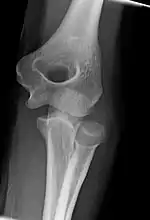

Left: Lateral X ray of a dislocated right elbow

Right: AP X ray of a dislocated right elbow

X-ray of ventral dislocation of the radial head. There is calcification of annular ligament, which can be seen as early as 2 weeks after injury.[29]